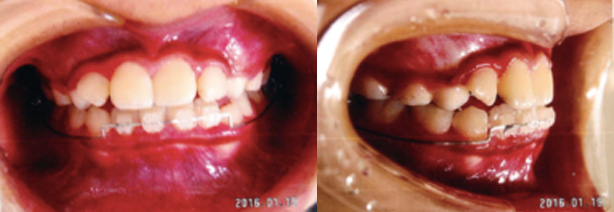

受け口(反対咬合)

通常上の歯と下の歯を噛み合わせた場合、上の歯が下の歯の前にきますが、反対に下の歯が上の歯の前に来ている状態を、受け口(反対咬合)と言います。

治療前

治療後